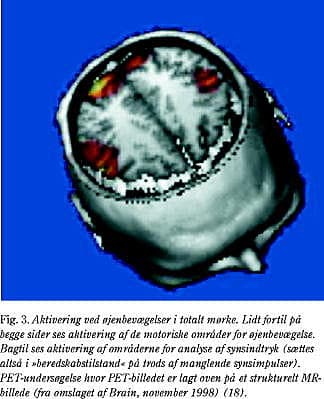

I forlængelse af disse undersøgelser udførtes studier af tilfældige, frivillige øjenbevægelser i mørke. Fra dyreeksperimentelle undersøgelser ved man, at der findes områder i den occipito-parietale cortex, som aktiveres som følge af proprioceptiv feedback fra øjenmusklerne. Disse occipito-parietale områder modtager således dels oplysninger om, hvorledes øjnene er placeret i forhold til kraniet og dels feedback fra de motoriske områder i det føromtalte frontale blikcenter. Det frontale blikcenter sender formentlig information om den tilsigtede bevægelse, så det indre kort af omverdenen (antagelig placeret i parietallappen) kan forberedes, før øjenbevægelsen finder sted. Undersøgelserne viste, at der som forventet var aktivering af det frontale center for øjenbevægelser. Herudover fandtes en udtalt aktivering af de visuelle associationsområder, men ikke af den primære visuelle cortex, som ligger helt bagtil i occipitalpolen (Fig. 3) (20). Forventningen om at skulle analysere nye synsinput sætter således hele den visuelle associationscortex i en beredskabstilstand, så den er aktiveret og »koncentreret« om den nye opgave.

Hertil kommer, at man er begyndt at kombinere oplysninger fra flere forskellige billedmodaliteter. For at kunne dette skal disse billeder oprettes i forhold til hinanden og efterfølgende overlejres oven på hinanden, så man er i stand til at anvende de stærke sider ved hver enkelt modalitet. For eksempel kan anatomiske MR-billeder (høj opløsning) overlejres med funktionelle PET-billeder (lav opløsning), så man er i stand til få mere præcise oplysninger om de områder i hjernen, hvor der finder funktionel aktivering sted (Fig. 3, Fig. 4 og Fig. 5). Det kræver moderne computerteknologi at håndtere disse store datamængder, og der ligger en stor indsats i at optimere processerne, hvor billeder oprettes enten baseret på matematiske vægtfunktioner eller evt. manuel definition af punkter/strukturer, der kan genkendes i de forskellige billedmodaliteter. Yderligere ligger der megen viden bag optimering af den måde, hvorpå billederne overlejres, det være sig valget af farveskalaer, kontraster, samt evt. ekstraktion af strukturer (segmentering af hjernen). (URL: http://nru.dk/research/illustrations/ eller http://hendrix.imm.dtu.dk/). For at tydeliggøre de aktiverede områder arbejdes der ofte med 3D-projektioner, så man på computerskærmen er i stand til at »bevæge sig frit i rummet udspændt af hjernen« - såkaldt virtual reality-visualisering.